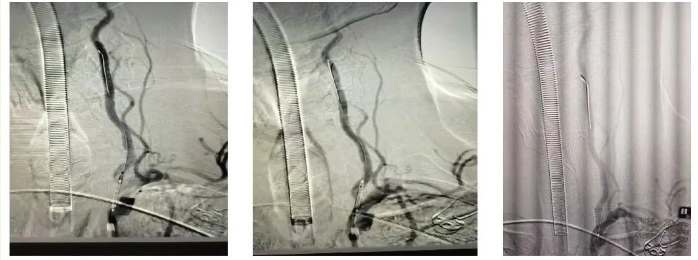

抽吸结束后,发现基底动脉下段可见斑块伴严重狭窄,球囊扩张

江顺福表示,完成抽吸后造影发现基底动脉下段仍存在问题,遂利用同轴输送技术成功植入椎动脉支架,解决血管狭窄问题,历时1.5小时,顺利完成手术。

术后,处理椎动脉起始部病变,给予球扩支架